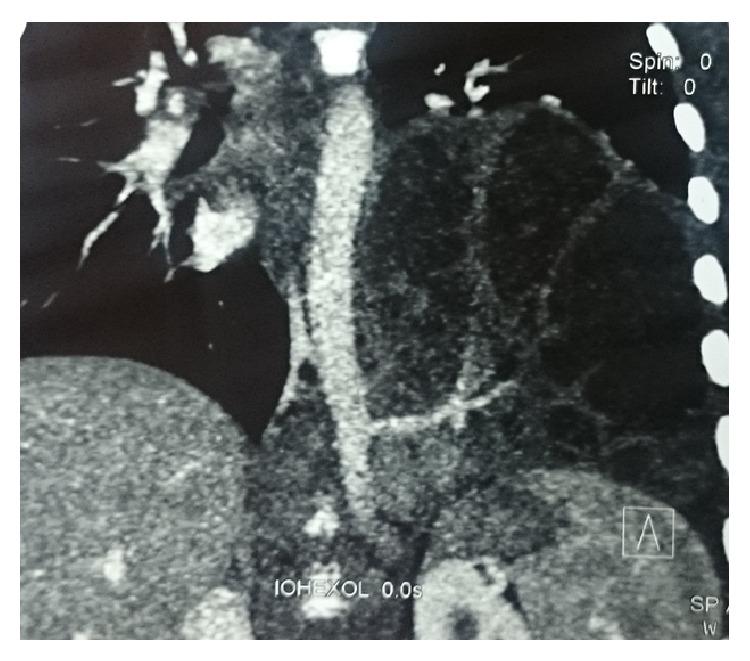

Intralobar sequestration is characterized by aberrant formation of nonfunctional lung tissue that has no communication with the bronchial tree and receives systemic arterial blood supply. Failure of earlier diagnosis can lead to recurrent pneumonia, failure to thrive, multiple hospital admissions, and more morbidity. The aim of this case report is to increase the awareness about the lung sequestration, to diagnose and treat it early, so that it is resected before repeated infection, and prevent the morbidity and mortality.

肺叶内型肺隔离症的特征是形成无功能的肺组织,该组织与支气管树无交通,并接受体循环动脉供血。早期诊断失败可导致反复肺炎、生长发育不良、多次住院及更多的发病率。本病例报告的目的是提高对肺隔离症的认识,早期诊断和治疗,以便在反复感染前进行切除,预防发病率和死亡率。